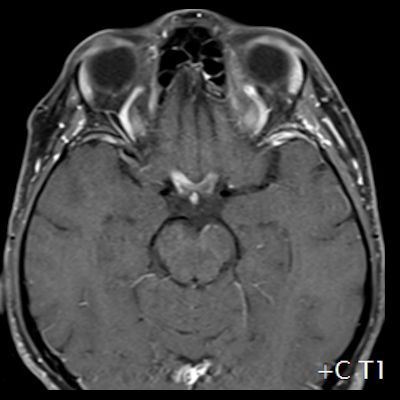

- (A) Torakal MRG’de sagital görüntülerde üst-orta torakal düzeyde T2A hiperintens (oklar), T1A izo-hipointens (ok) uzun segment ekspansil sinyal değişikliği izlenmekte olup sagital postkontrast T1A’da kontrast tutulumu mevcuttur (oklar). Bulgular longitudinal ekstensif transvers miyelit (LETM) ile uyumludur.

- (B) Orbita MRG’de aksiyel yağ baskılı T1A’da optik sinir prekiazmatik segmenti (oklar) gösterilmiş olup sırası ile aksiyel ve koronal post-kontrast yağ baskılı T1A görüntülerde bilateral optik sinir prekiazmatik segmentte kontrast tutulumu dikkati çekmektedir (oklar ve daire).

- Optik nörit varlığında özellikle optik kiazma ve posterior optik sinir tutulumu görülür ve bilateral olabilir.

- MS’de optik nörit radyolojik tutulumu daha fokal iken NMO spektrum bozukluğu ve MOGAD’de genellikle daha yaygındır. MOGAD, NMO’ya kıyasla daha anterior kısmı etkileme eğilimindedir.

- Kontrast madde enjeksiyonu sonrasında neredeyse tüm akut NMO lezyonları, yamalı, düzensiz veya periferik olarak kontrastlanma gösterir.